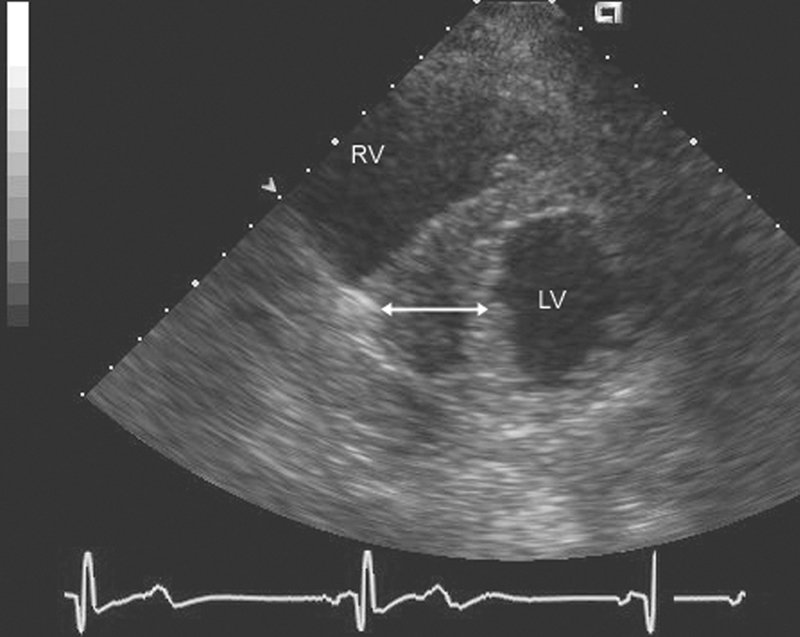

فحوصات تشخيصية لبعض امراض القلب والشرايين التاجية